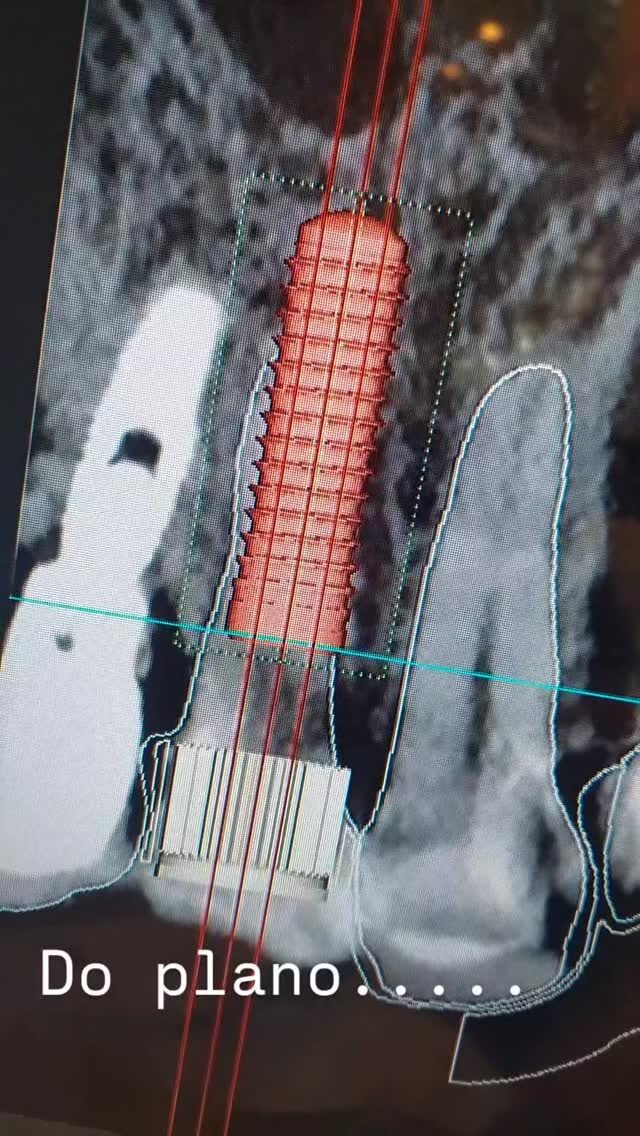

Cirurgia Ortognática

Você sente dificuldade para morder, falar ou até mesmo respirar corretamente? A Cirurgia Ortognática pode ser a solução! Esse procedimento corrige alterações ósseas no maxilar e mandíbula, melhorando a função mastigatória, a harmonia facial e a qualidade de vida.

Os implantes dentários substituem dentes perdidos por meio de pinos de titânio inseridos no osso maxilar ou mandibular, que suportam próteses fixas. Proporcionam estética e funcionalidade semelhantes aos dentes naturais, sendo uma solução duradoura e segura.